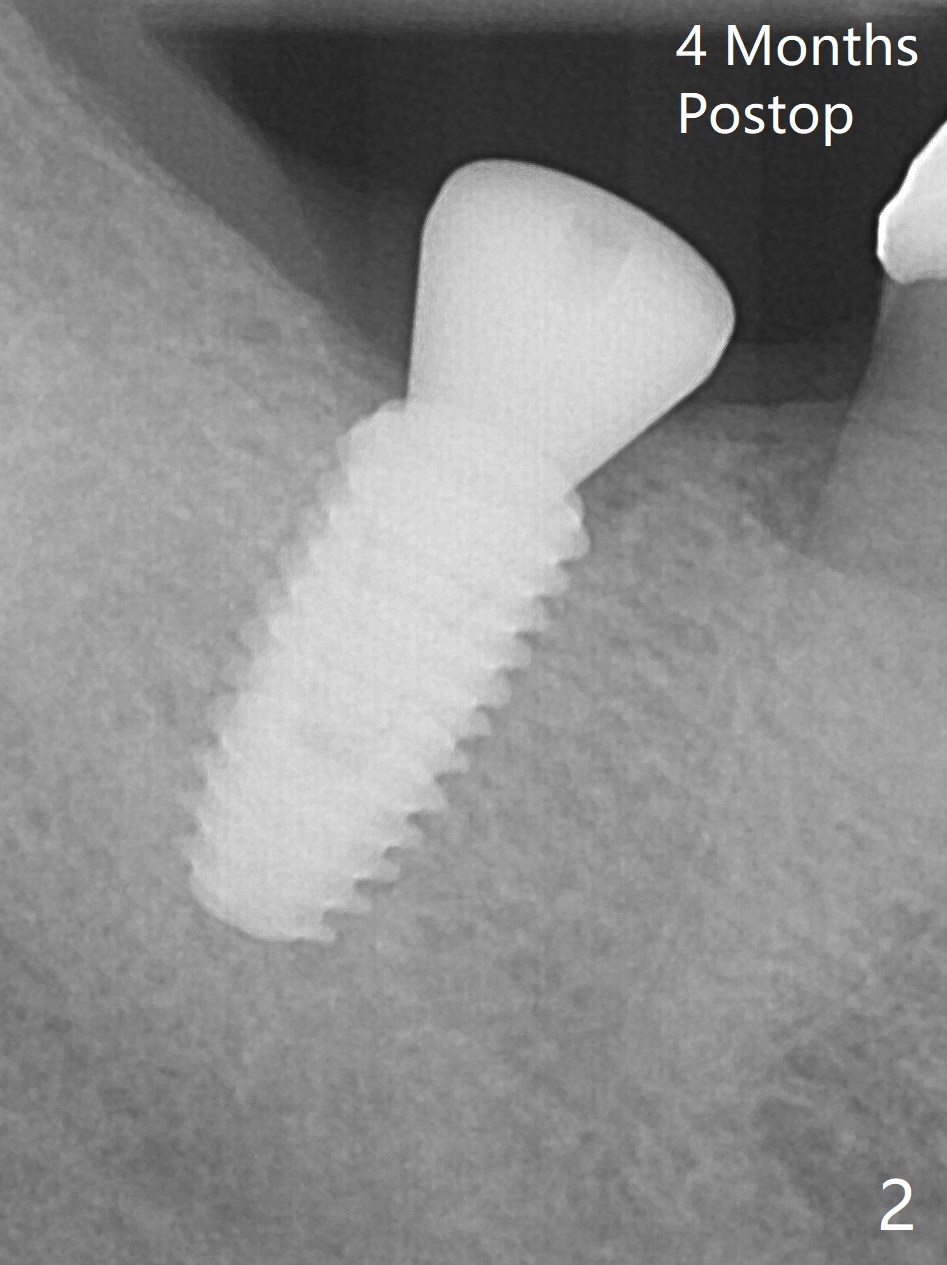

Two carpules of anesthetic is administered at #30 for the apprehensive patient, as compared to one for most cases. He is extremely pleased when the guided surgery is finished in a quick and painless manner (Fig.1). There is no bone loss 4 months postop (Fig.2); impression is taken.